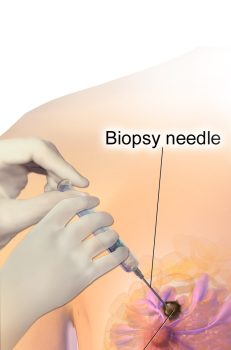

3.5. Sinh thiết

Nếu nghi ngờ ung thư vú, bác sĩ sẽ sinh thiết một phần mô vú để bác sĩ giải phẫu bệnh khảo sát dưới kính hiển vi.

Hình 2. Sinh thiết vú